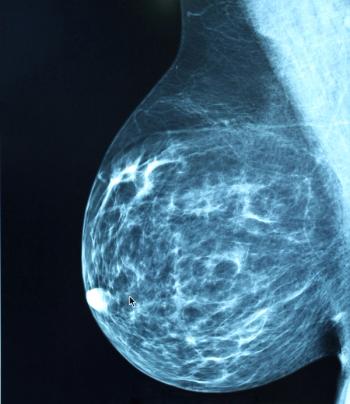

A recent study found breast arterial calcification on mammograms could help predict higher risk of stroke, cardiovascular death, and heart disease in women.